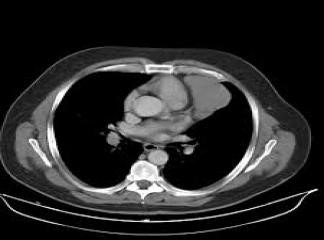

Sepsisli xəstələrdə rentgenoloji müayinədə mediastinumda hava görünməsi yüksək şübhə əlamətidir (Şəkil 9).

Şəkil 9. Mediastinal emfizema

Şəkil 10. KT. Kontrastın qida borusundan ekstravazasiyası

Kəskin mediastinitin diaqnozunu dəqiqləşdimək üçün ən vacib müayinə KT-dir. KT-də divararalığında ödem, maye, hava, kontrast ekstravazasiyası mediastinitin xarakterik əlamətləridir.

- KT-də divararalığında ödem, maye, hava, bəzən də kontrast ekstravazasiyası (Şəkil 10)